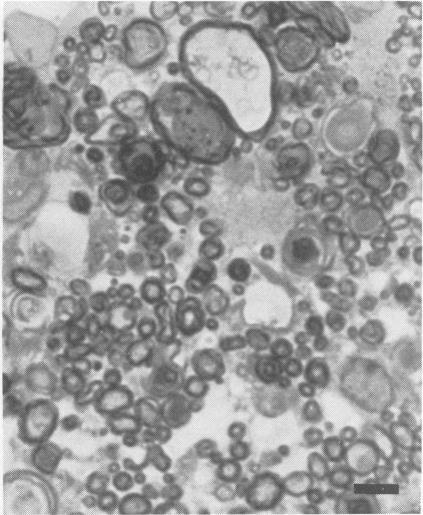

Wistar rats subjected to a single exposure lasting six hours to ethylene oxide (EO) at a concentration of 500 parts per million three times a week for 13 weeks developed ataxia in the hindlegs. Myelinated fibres in hindleg nerves and in the fasciculus gracilis showed axonal degeneration sparing the nerve cell body of the lumbar dorsal root ganglion and myelinated fibres of lumbar dorsal and ventral roots. These pathological findings are compatible with central-peripheral distal axonal degeneration. This is the first animal model of EO neuropathy to be histopathologically verified.

将Wistar大鼠每周三次暴露于浓度为百万分之500的环氧乙烷(EO)中,每次暴露持续6小时,持续13周,大鼠后肢出现共济失调。后肢神经和薄束中的有髓纤维显示轴突变性,而腰背根神经节的神经细胞体以及腰背根和腹根的有髓纤维未受影响。这些病理发现与中枢 - 外周远端轴突变性相符。这是首个经组织病理学证实的EO神经病变动物模型。